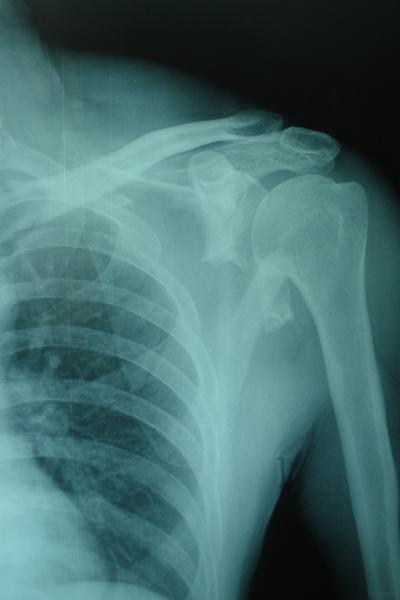

[localimg=400,267]6[/localimg][localimg=400,267]5[/localimg]患者男性,65岁,从2米高处摔下,左肩部着地,即感左肩部肿痛伴活动不利,当时无昏迷、无意识丧失,由家人送入院。

查体:左肩部肿胀,压痛明显,肩关节活动不利,指端血供、感觉、活动均正常。

初步诊断:左肩胛骨粉碎性骨折